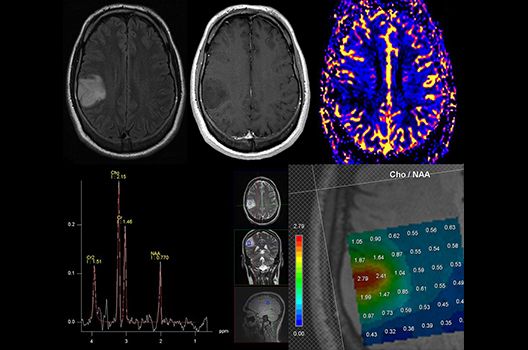

Die Schwerpunkte in der MR-Forschung liegen in der multiparametrischen und funktionellen Bildgebung bei onkologischen und anderen, neuroradiologischen Fragestellungen und umfassen die Anwendung modernster MR-Verfahren sowie die Untersuchung an Hochfeld-Geräten.

Die Magnetresonanztomographie (MRT) ist ein Verfahren, bei dem durch magnetische Kräfte Bilder des Körperinneren angefertigt werden. In der Neuroradiologie können manchmal kleinste Veränderungen schwere Folgen haben; daher forschen wir an der Entwicklung hochauflösender MRT-Sequenzen, mit denen diese Prozesse und auch einzelne Nervenfaserbahnen sichtbar gemacht werden können. Darüber hinaus sind bei vielen Erkrankungen des Gehirns die Blutgefäße betroffen. Daher arbeiten wir an der Neu- und Weiterentwicklung von MRT-Sequenzen zur Darstellung der Blutgefäße und zur Blutflussanalyse (sog. „Angio-MRT“). Einen besonderen Forschungsschwerpunkt unserer Klinik stellen die MR-Protonenspektroskopie und die funktionelle MRT dar, mit denen die Analyse einzelner chemischer Substanzen im Hirngewebe oder die Darstellung ausgewählter Hirnfunktionen möglich ist.

Die Hybridbildgebung mittels PET/MRT spielt insbesondere in der onkologischen Bildgebung eine wichtige Rolle. Eine mögliche Fragestellung ist die Unterscheidung zwischen einem Tumorrezidiv oder therapeutisch assoziierten Veränderungen insbesondere dann, wenn diese Frage mittels MRT alleine nicht beantwortet werden kann.

Die bildgebende Diagnostik und Verlaufsbeurteilung von Tumoren des Nervensystems ist einer der klinischen und Forschungsschwerpunkte unserer Abteilung. Eine besondere Bedeutung kommt der Hybrid-Bildgebung zu. Das Universitätsklinikum verfügt über einen integrierten Ganzkörper-PET/MRT-Scanner, der die Vorteile der MRT-Bildgebung und der Positronenemissionstherapie (PET) vereinigt. Aufgrund der langjährigen klinischen Arbeit und Forschungstätigkeit mit diesem Gerät hat die Neuroradiologie Tübingen maßgeblich zur Etablierung dieses Verfahrens beigetragen. Auch weiterhin forschen wir intensiv an neuen Methoden zur frühen Einordnung von Tumoren und insbesondere Tumorrezidiven, die mit anderen Methoden häufig nicht erfasst werden können.